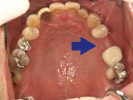

54歳女性

部分義歯がどうしても違和感が強くて、できれば義歯を使わなくてもいいようにしたいとのこと。

下顎はそんなに問題ないですが、上顎は骨の厚みと量、共に乏しく本来はインプラントは不可能です。

あきらめずに、かなり高度な技術ですが骨を増やす手術を併用してなんとか植えることができました。

術前

↓↓↓↓

術後